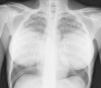

Varón de 35 años, transexual, originario de Colombia. Vive en España desde 2009. Antecedentes de cirugía estética mamaria y glútea en 2005. Consulta en agosto de 2011 por fiebre asociada a astenia, pérdida de peso y sudoración nocturna desde hace 2 meses, así como signos de deshidratación y desnutrición. Analíticamente destaca una hiponatremia (124 mEq/l), aumento de LDH (1.053 UI/l), colestasis (bilirrubina directa 1,3mg/dl, FA 1.410 U/l, GGT 211 UI/l), linfopenia (300/ml), y aumento de marcadores inflamatorios (VSG 73mm/h, PCR 7mg/dl). Una radiografía de tórax evidencia un patrón miliar bilateral (fig. 1) y en una ecografía abdominal destaca una hepatomegalia homogénea. Se solicita serología urgente combinada para VIH (antígeno p24 y anticuerpos para VIH 1 y 2 por ELISA), virus hepatotropos, VDRL, antígeno para Cryptococcus neoformans, reacción intraepidérmica de Mantoux y ELI-SPOT TBC. Se toman muestras de hemocultivos para microorganismos comunes y micobacterias, urinocultivo, y se realiza fibrobroncoscopía con lavado broncoalveolar (LBA) de lóbulo medio para la detección de microorganismos comunes, micobacterias, hongos, virus y Pneumocystis jirovecii, así como muestra de esputo post-LBA. Con la orientación de tuberculosis miliar y posible sobreinfección bacteriana, se inicia tratamiento empírico con tuberculostáticos (isoniazida 75mg-rifampicina 150mg-pirazinamida 400mg-etambutol 275mg) y ceftriaxona 1g ev c/24h.